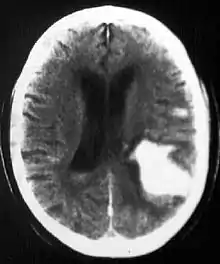

In the elderly population, amyloid angiopathy is associated with cerebral infarcts as well as hemorrhage in superficial locations, rather than deep white matter or basal ganglia. These are usually described as "lobar". These bleedings are not associated with systemic amyloidosis.